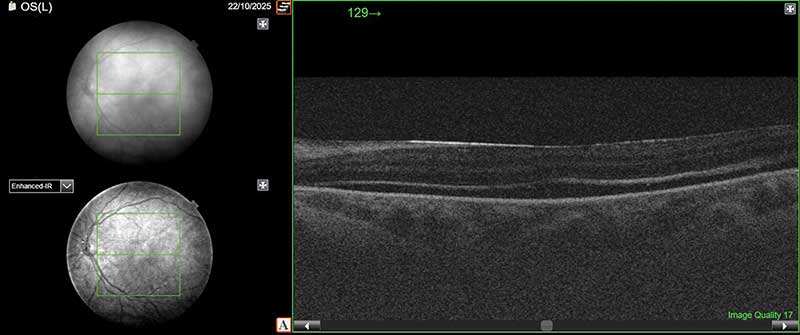

Рис. 3. ОКТ макулярной области левого глаза после второго этапа операции (удаление силиконового масла; сетчатка прилежит, фиксируются единичные мелкие интра- и субретинальные полости. Архитектоника слоев сохранена)

Контрольные осмотры через четыре и шесть недель: острота зрения повысилась до 0,3, сетчатка прилежит, зона ретиношизиса не визуализируется, разрывы отграничены стойкими хориоретинальными рубцами, ВГД – 20 мм рт. ст. (без гипотензивной терапии). По данным ОКТ макулярной области отмечается прилегание сетчатки с сохранением единичных мелких полостей субретинальной жидкости (рис. 3).